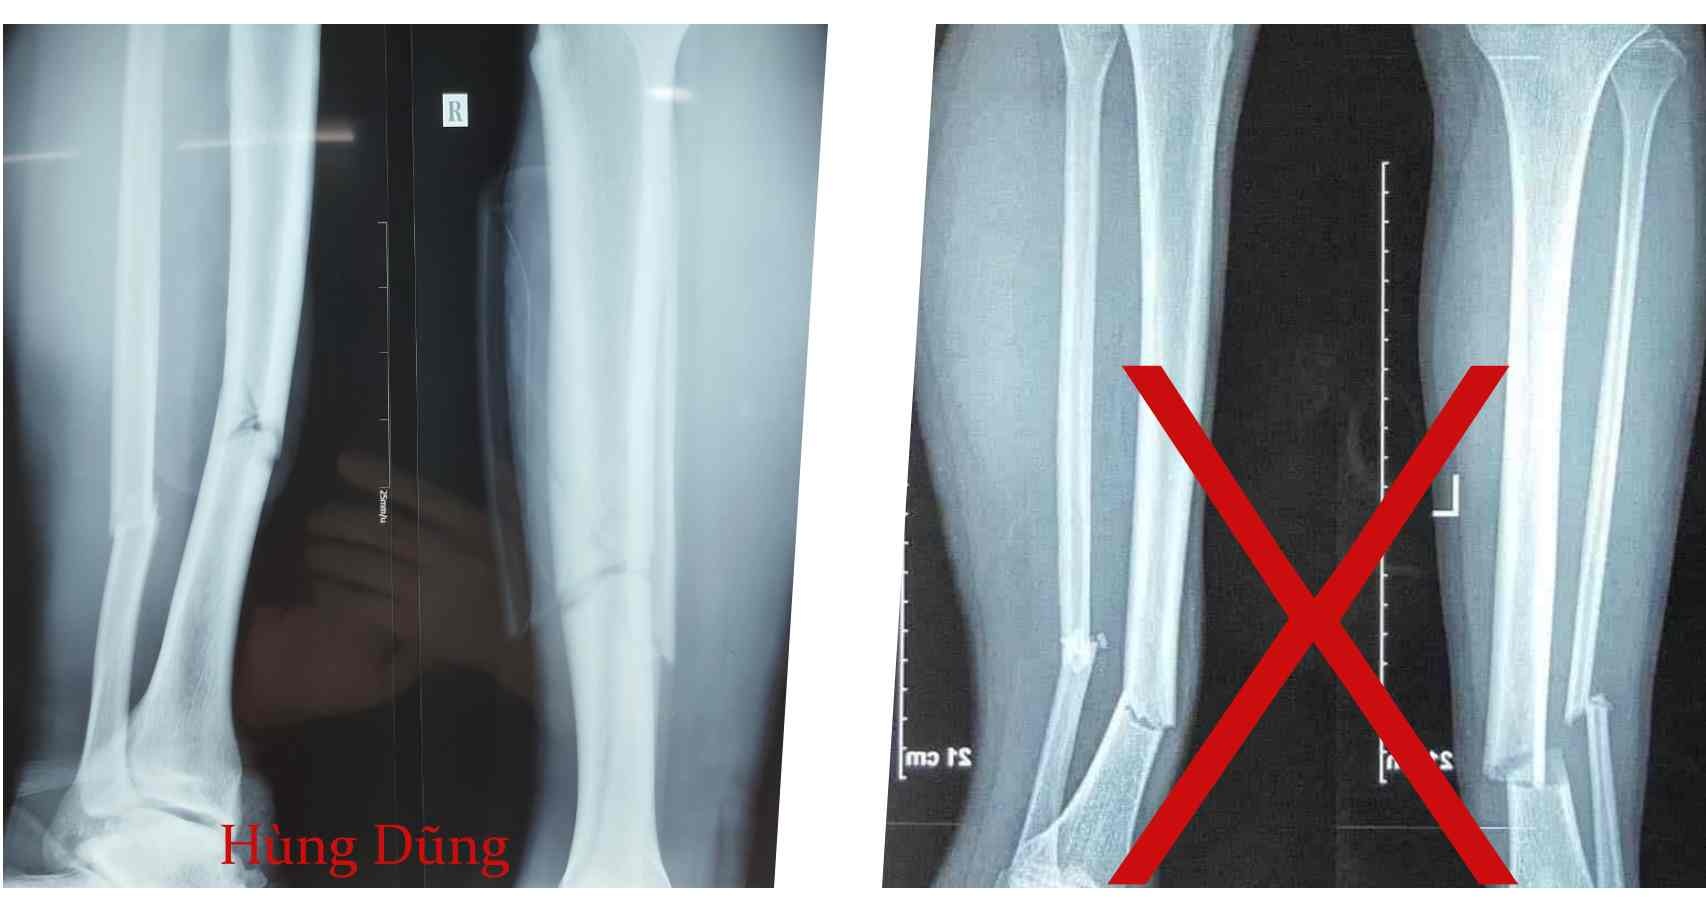

Đó là một tấm phim gãy 1/3 xương ống khuyển, giống chẩn đoán của Hùng Dũng. Tuy nhiên, nếu để ý kỹ, phim X-quang giả ghi chữ L (tức là Left - chân trái), trong khi Dũng bị gãy chân phải.

Hai phim X-quang khác nhau, một của Hùng Dũng (trái) và một là giả mạo.

CLB Hà Nội nhanh chóng đính chính, phim X-quang trên mạng xã hội không phải của Hùng Dũng.

Đại diện CLB Hà Nội mong muốn mọi người không lan truyền những hình ảnh sai lệch liên quan đến chấn thương của Hùng Dũng. Thông tin chính thức là Dũng bị gãy 1/3 xương ống khuyên bên phải.